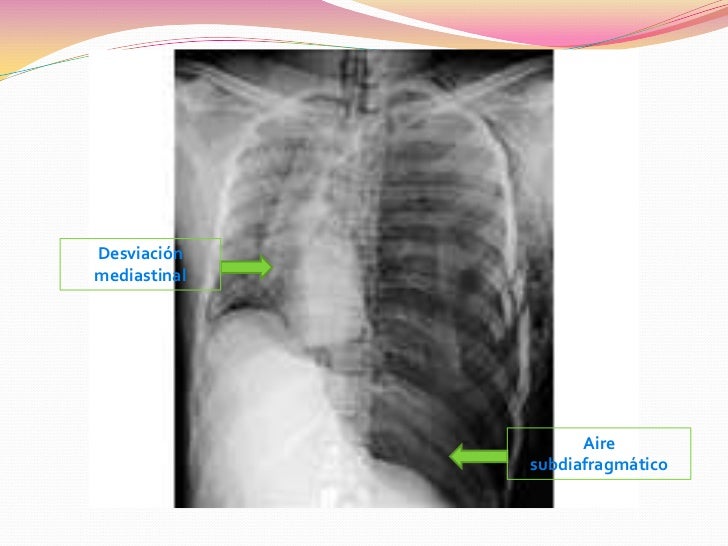

3.- neumotorax a tension: resulta de una lesion abierta en torax por la cual va ingresar aire a la cavidad pleural ocasionando que se llene de aire y desplazando el otro pulmon hasta colapsarlo.

-Disnea, -Ansiedad, -Desviacion de la traquea, -Ruidos respiratorios disminuidos de lado afectado, -Hipotension.

Al momento que se confirme un neumotorax se debe realizar una descompresion inmediata con aguja